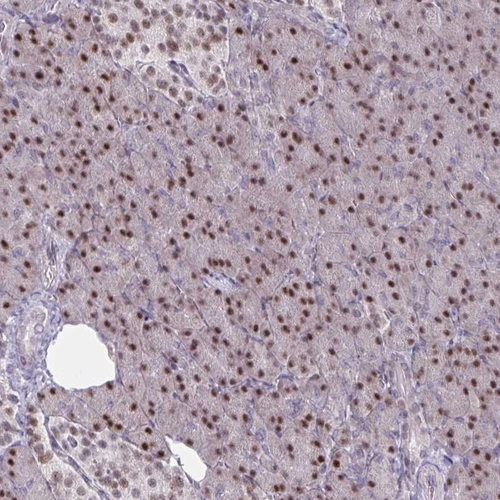

Immunohistochemical staining of human kidney shows strong nuclear positivity in cells in tubules.